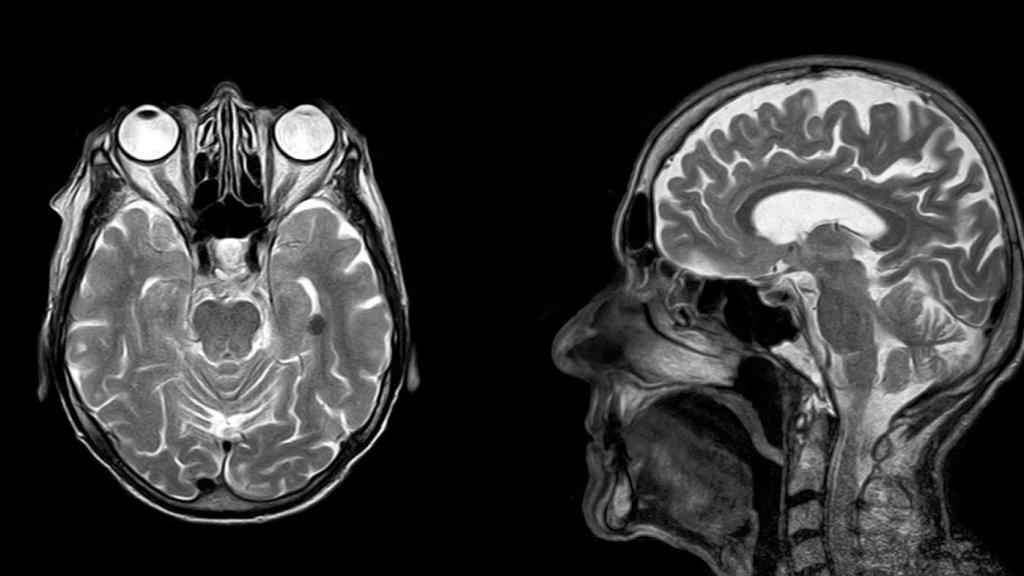

Nuevo malware hace que aparezcan tumores cancerígenos en nuestras radiografías

Un nuevo malware de escáner tomográfico y resonancia magnética es capaz de modificar los resultados, haciendo creer a los médicos que tenemos cáncer.

Los escáneres de tomografía y de imagen por resonancia magnética son valiosas herramientas para comprender mejor el interior de nuestro cuerpo. Ofrecen grandes ventajas respecto a un escáner de rayos X convencional. Como la posibilidad de obtener imágenes en todos los ángulos posibles en el caso de las tomografías; o la de obtener imágenes secuenciales en secciones del cuerpo en el caso de la resonancia magnética.

Estas imágenes son muy útiles, especialmente para descubrir tumores cancerígenos. Pueden ser vitales para comprender mejor la localización y el alcance del cáncer, para conseguir el mejor diagnóstico y por lo tanto, el tratamiento adecuado. Aunque a veces es normal encontrarse con artefactos visuales en estas pruebas (sobre todo si el paciente se ha movido), suelen ser bastante fiables.

Sin embargo, los modernos aparatos usados para realizar estas radiografías están conectados a la red del hospital para poder enviar los datos a un ordenador cercano; y por lo tanto, son susceptibles a ataques de hackers, como ha demostrado unos investigadores israelíes, que han desarrollado un malware especialmente diseñado para atacar este tipo de escáneres CT (tomográficos) y MRI (de resonancia magnética).

Los investigadores querían demostrar lo vulnerables que son estos aparatos médicos normalmente, y lo efectivos que pueden ser los ataques a la red del hospital. Para ello, desarrollaron un malware que es capaz de modificar los resultados de estos escáneres para incluir falsos tumores cancerígenos; las imágenes resultantes eran modificadas de tal forma que no fuesen sospechosas para los médicos.

En las pruebas se demostró que estas radiografías modificadas eran capaces de engañar a todos los radiólogos; en las imágenes modificadas, los médicos presentaron un diagnóstico de cáncer el 99% de las ocasiones. Lo llamativo es que, incluso cuando les avisaban de que una imagen había sido modificada, el 60% de las ocasiones seguían creyendo que eran tumores reales.

También sirve para eliminar tumores de las radiografías

Que te diagnostiquen cáncer sin tenerlo ya es lo suficientemente malo, pero peor aún es que también funciona al contrario. El malware también es capaz de eliminar la presencia de tumores en las radiografías, y el 94% de las ocasiones los médicos afirmaron que el paciente estaba sano; si les avisaban de que las imágenes habían sido modificadas, el 87% de las veces no creían que el paciente tuviese cáncer, cuando en realidad sí lo tenía. Hasta el software usado para detectar tumores fue engañado de esta manera.

Este malware no ha sido publicado, y no hay indicios de que se esté usando en ataques contra hospitales; pero demuestra el gran problema de seguridad de los hospitales modernos, y que, en teoría, es perfectamente posible modificar los resultados de estas pruebas sin que nadie se de cuenta.